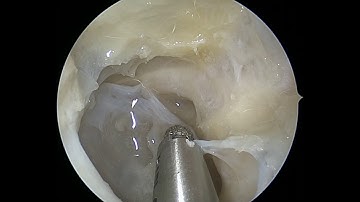

Optic nerve sheath decompression step by a step, step 7, re-inserting the MR and closing incision